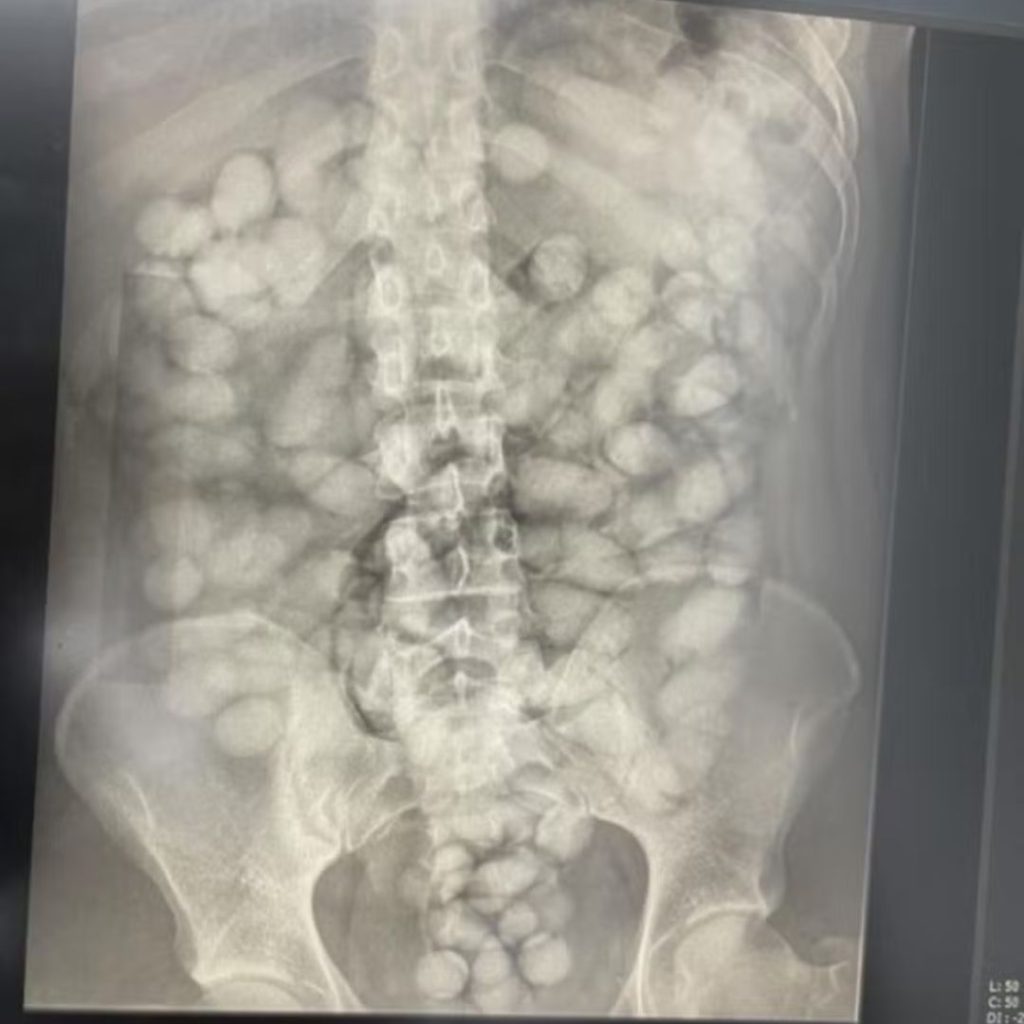

A operação Via Corporis teve início após a prisão de uma jovem de 20 anos, em outubro de 2024, no Aeroporto Internacional de Viracopos, em Campinas. Ela tentava embarcar para Paris com 1,3 kg de cocaína no organismo. A partir dessa apreensão, a PF identificou uma rede transnacional responsável por aliciar os chamados “correios humanos”, emitir passagens e custodiar toda a logística do crime.

O nome da operação, Via Corporis – expressão em latim para “caminho do corpo” – faz alusão à forma utilizada pelo grupo para ocultar a droga durante os voos internacionais.